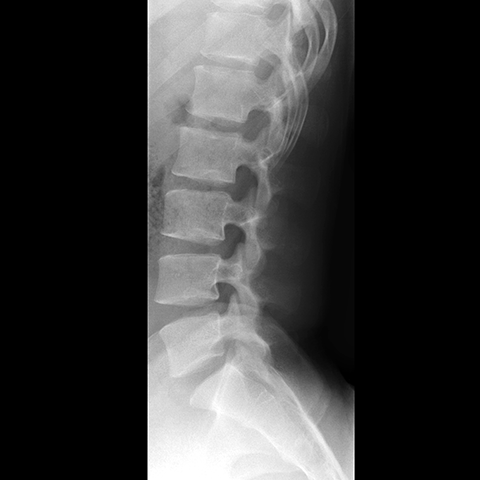

Lumbar Spine, plain film (lateral view) [2 of 4]